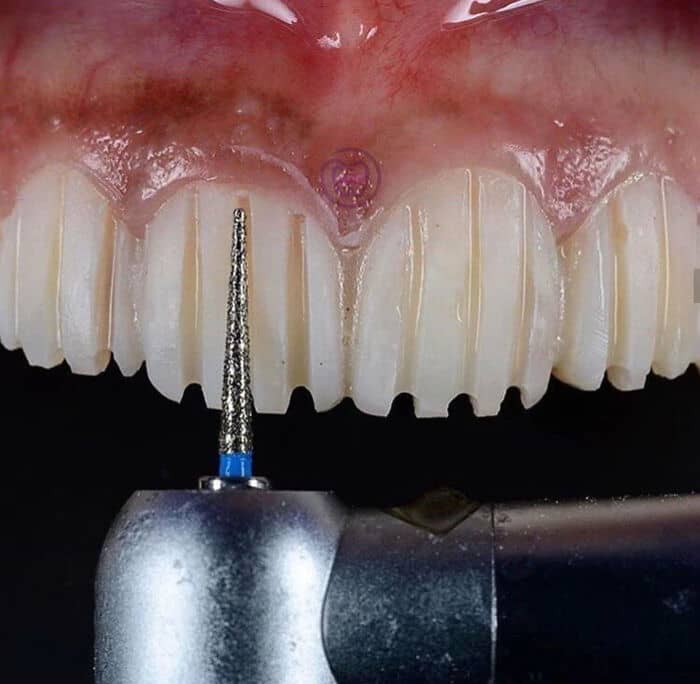

#47 Veneers Preparation